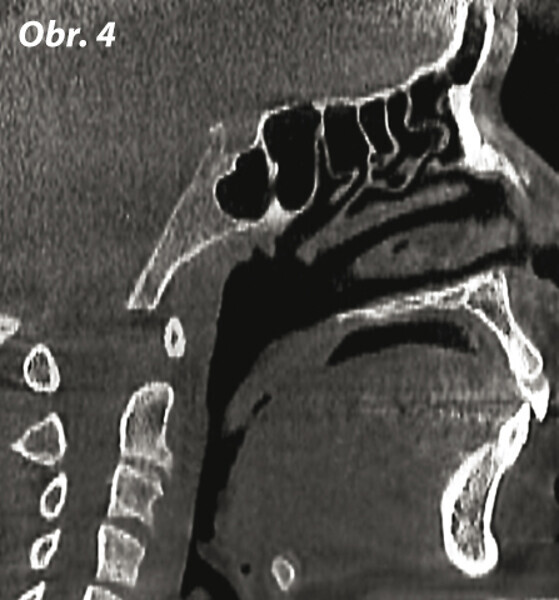

Význam 3D zobrazovacích systémů v současné ortodoncii